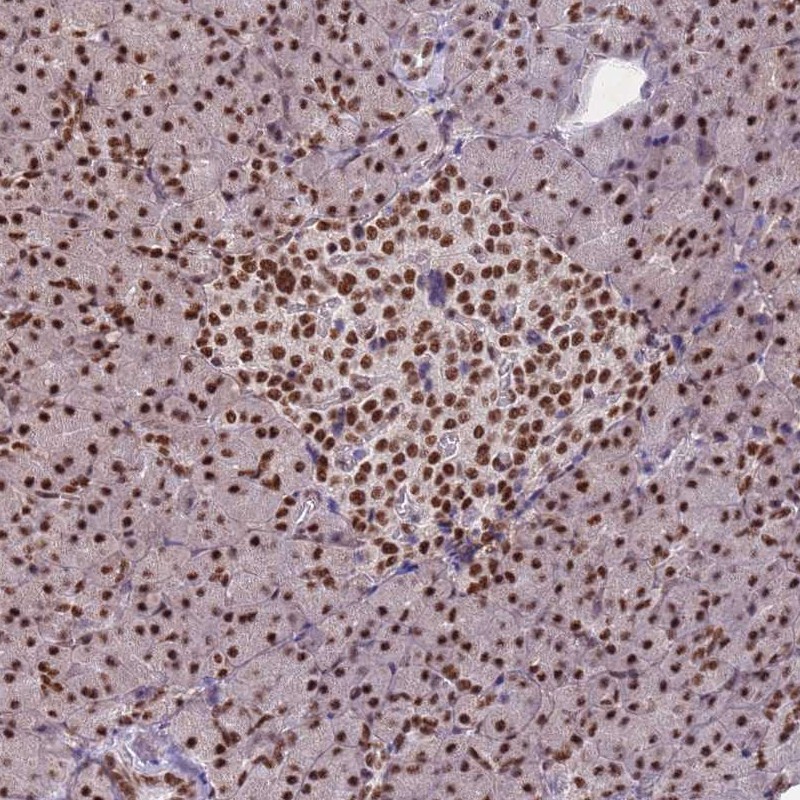

Immunohistochemical staining of human pancreas shows strong nuclear positivity in exocrine glandular cells and islets of Langerhans.